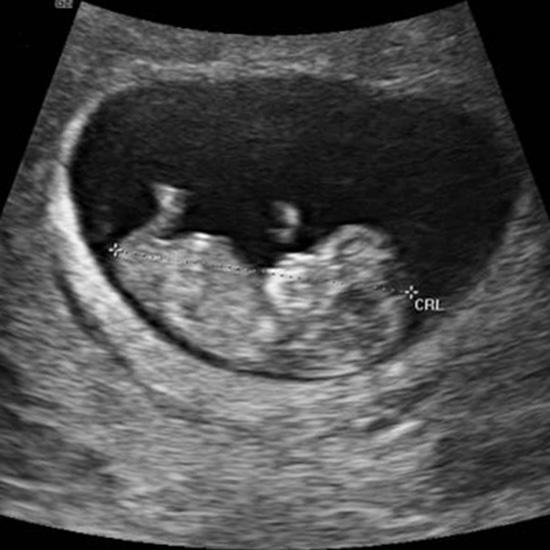

Happy Momma to be!!!! Almost through First Trimester yay

I cannot believe I am already 10 weeks into my first trimester!!! Look at my sweet little baby!! Seriously cannot wait to find out the gender ahhh omg I am so blessed!